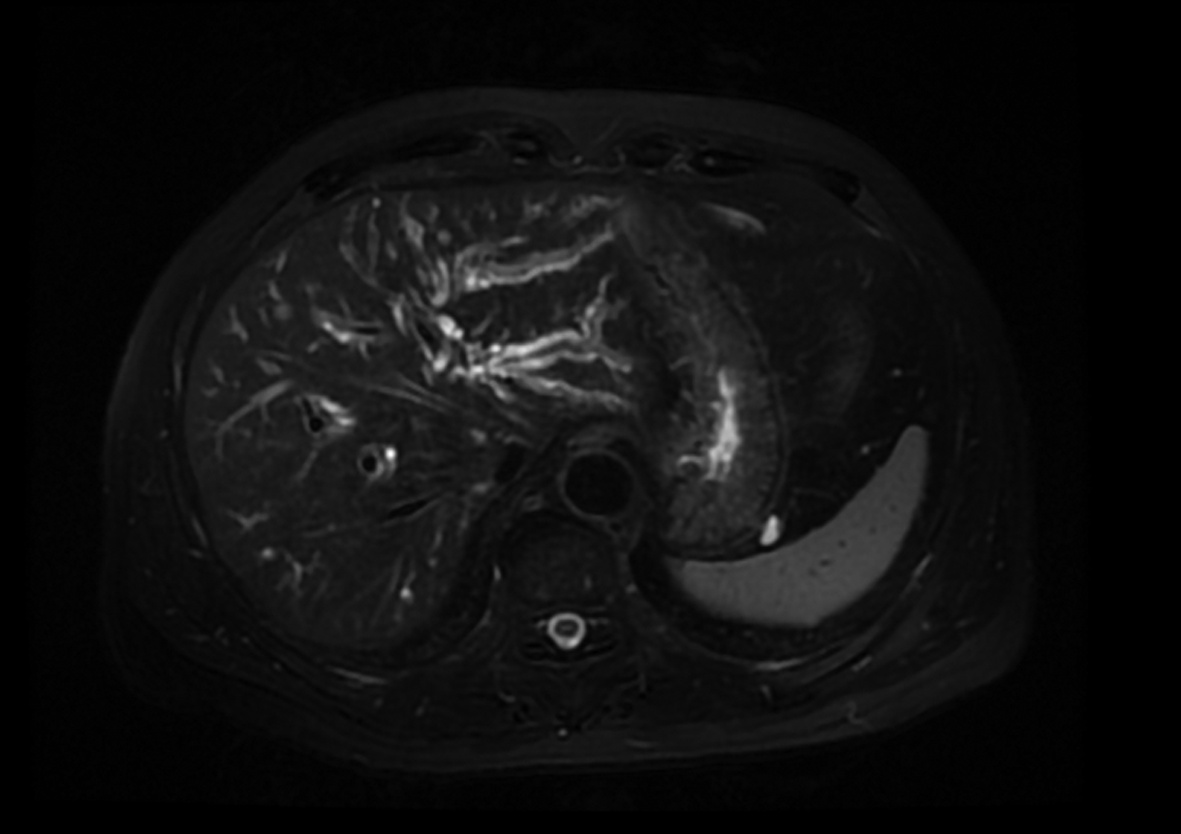

A case of spontaneous hepatic rupture and hemorrhage after liver transplantation

Jian MA, Lihong HE, Lingyun WANG, Yanan ZHAI, Xun LI, Lei ZHANG

2022, 38(4): 891-893. DOI: 10.3969/j.issn.1001-5256.2022.04.030

Abstract(985) HTML (354) PDF (3041KB)(37)

Abstract: